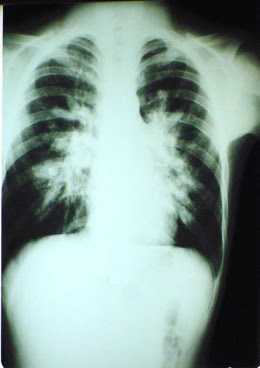

Chest x-ray (picture 7-8) surveys in certain geographic areas have demonstrated many resi dents with symptomless, nontuberculous, occasionally calcified pulmonary le sions; delayed cutaneous hypersensitivity reactions to histoplasmin suggest widespread but subclinical infection. The highest incidence of such hypersensitiv ity is in the Ohio and Mississippi River valleys.

The view is taken central. The size of the left lobe is reduced and the margins of left hemidiaphragm, the lower left heart margin and the costophrenic recess are obscured by a density that has a clear central margin as it extends into the left axilla, implying a pleural density. There is shadowing at the apex of both lungs. This is well-defined and irregular with calcifications. The right hilar vessels are vertical and sparse in both upper zones with elevation of the hilar point on both sides, implying loss of upper lobe volume. There is coarse linear calcification immediately above the diaphragm, well shown on the right and a little obscured on the left. In this particular view, no rib erosion is identified.